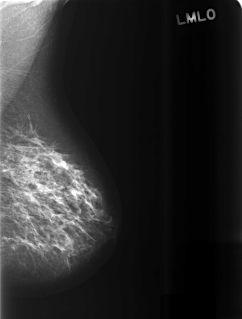

ics_version 1.0 filename C-0471-1 DATE_OF_STUDY 8 9 1997 PATIENT_AGE 48 FILM FILM_TYPE REGULAR DENSITY 2 DATE_DIGITIZED 28 12 1998 DIGITIZER LUMISYS LASER SEQUENCE LEFT_CC LINES 5696 PIXELS_PER_LINE 3520 BITS_PER_PIXEL 12 RESOLUTION 50 NON_OVERLAY LEFT_MLO LINES 5416 PIXELS_PER_LINE 4112 BITS_PER_PIXEL 12 RESOLUTION 50 NON_OVERLAY RIGHT_CC LINES 5768 PIXELS_PER_LINE 4056 BITS_PER_PIXEL 12 RESOLUTION 50 OVERLAY RIGHT_MLO LINES 5936 PIXELS_PER_LINE 4168 BITS_PER_PIXEL 12 RESOLUTION 50 OVERLAY |